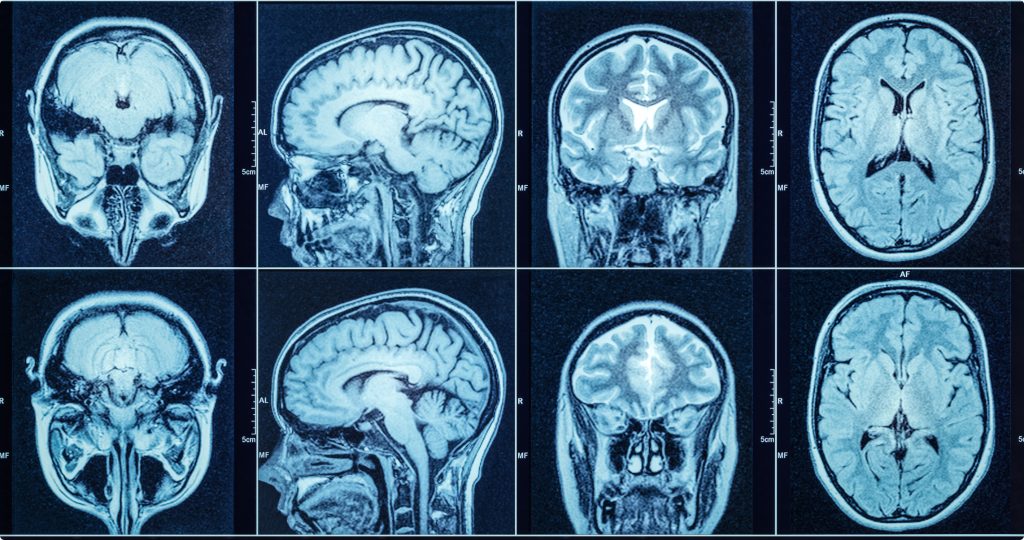

Купити МРТ буде вигідніше, коли необхідно буде діагностувати захворювання центральної нервової системи, опорно-рухового апарату та м’яких тканин. Ця техніка допомагає виявляти пухлини, запальні процеси та дегенеративні зміни. Особливо цінним цей метод діагностики стає за необхідності оцінити стан головного та спинного мозку. Крім того, МРТ використовується при дослідженнях суглобів, зв’язок та хрящів, де інші методи діагностики не дають достатньої інформативності.